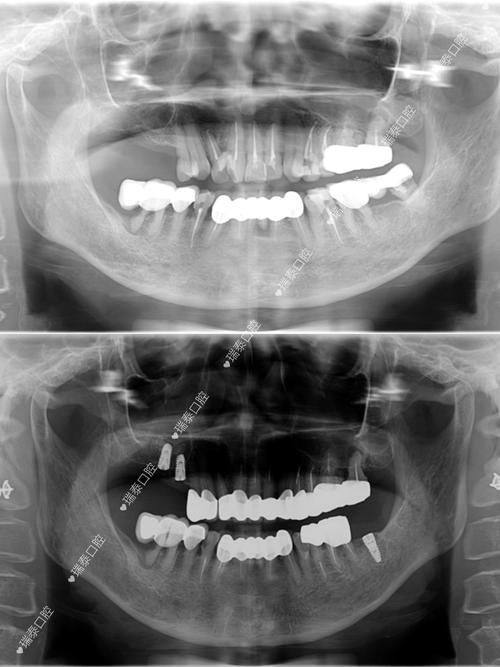

| 半口All - on - 4(韩系) | 39800元起 |

| 全口All - on - 6(瑞士) | 78000元起 |